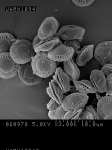

| Species Name: | Aspergillus spinulosporus |

| Taxonomy: | FUNGI Ascomycota, Eurotiomycetes, Eurotiales, Aspergillaceae |

| Characters: | CULTURE CONDITIONS heavy ascomata on PDA - // HUMAN/ ANIMAL PATHOGEN cerebral aspergillosis in a small bowel transplant patient - // MOLECULAR SYSTEMATICS calmodulin sequence has 99% identity to 5 strains of E. echinulata in the GenBank - fide P. Iwen (Click for publications citing UAMH 10948) |